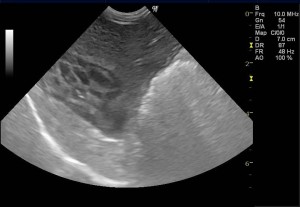

以前より胆嚢内の粘液腫様変性が認められていたため注意して経過観察を実施していた症例です。超音波では、胆嚢の拡張は認められないものの、内部の変性(キウイフルーツ様パターン)は顕著に認められました。

本症例は数か月ごとに超音波検査にて胆嚢を観察し、拡張や内部の変性異常が強く認められた時点で手術を行っていきました。破裂する前、肝障害や黄疸が起きる前の対応です。

診断:胆嚢粘液嚢腫